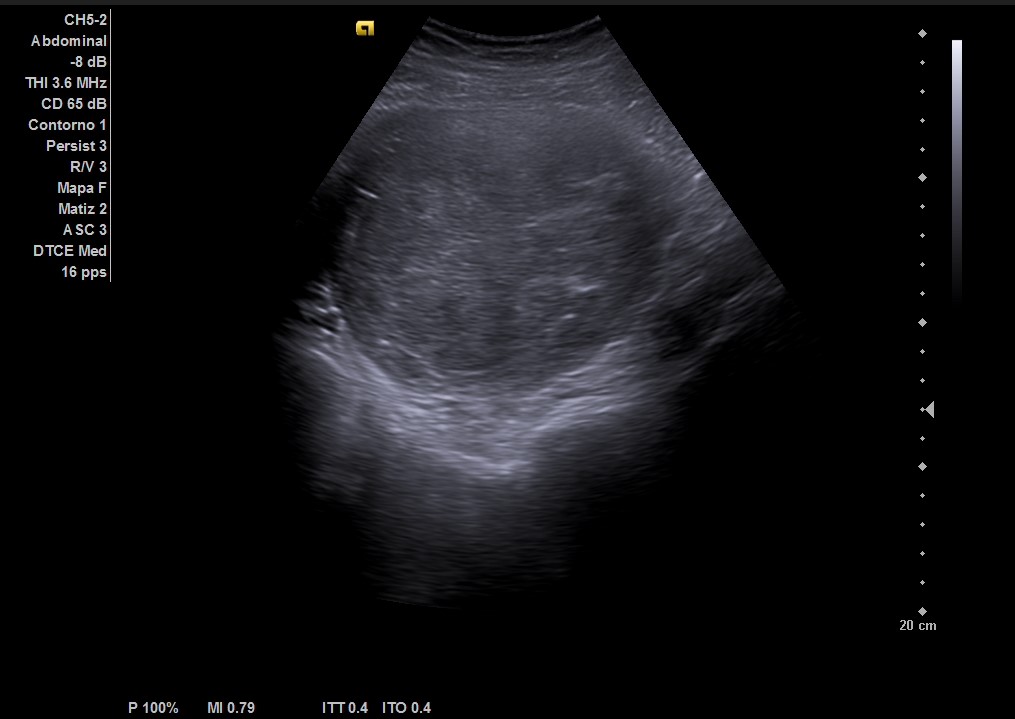

Ecografía abdominal: masa heterogénea de 10 x 10 cm dependiente de útero con vascularización periférica. No se observa la vejiga al estar repleccionada y desplazada por dicha masa. Se vuelve a hacer ecografía con vejiga llena y se observa cómo deforma la pared por efecto masa. Vejiga sin litiasis en su interior, no globo vesical.